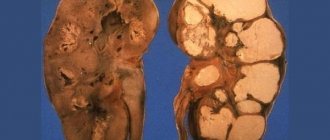

Болезнетворные бактерии вызывают в тканях воспалительный процесс – пиелонефрит, пиелит или гломерулонефрит. Эти заболевания и известны как воспаление почек. Воспалительный процесс может быть односторонним или затронуть обе почки.

Острый пиелонефрит – инфекционный воспалительный процесс, поражающий почечную паренхиму (собственно ткань органа), лоханку и чашечки. Симптомы застужения почек — это внезапное повышение температуры до 39-40 С, озноб, проливной пот, головная боль и выраженная с присоединением тошноты, рвоты и нарастанием головной боли. А также признаки застуженных почек проявляются в виде ухудшения общего самочувствия (нарастающей слабости и недомогания), жажды, нарушения мочеиспускания (в связи с воспалением и отеком мочеточников) и появление мутной мочи, с наличием в ней крови, солей и песка.

Хронический пиелонефрит может возникать как следствие неизлеченного острого пиелонефрита или при полном отсутствии лечения (первично-хронический пиелонефрит), особенно если это остро застуженные почки и симптомы протекали на фоне вирусной или бактериальной инфекции, а в дальнейшем проявлялись только периодами необъяснимой лихорадки при обострении болезни. В данном случае диагноз заболевания нередко представляет большие трудности и выявляется только при полном комплексном обследовании пациента.

Гломерулонефрит – это сложный воспалительный процесс с преимущественным поражением сосудов клубочков. Наиболее часто это заболевание возникает после ангин, тонзиллитов, скарлатины или инфекций верхних дыхательных путей (пневмоний, гнойных бронхитов), а также после переохлаждения организма во влажной среде так называемый «окопный» нефрит.

При гломерулонефрите симптомы простуды почек проявляются в виде появления отеков на лице, на фоне выраженной бледности кожных покровов (лицо «нефритика»), появлением крови в моче и повышение артериального давления. Если простужены почки, то симптомы при гломерулонефрите у лиц молодого возраста могут проявляться признаками сердечной недостаточности (одышка при физической нагрузке, боли в сердце), нарушениями на ЭКГ, появлением крови и белка в моче.